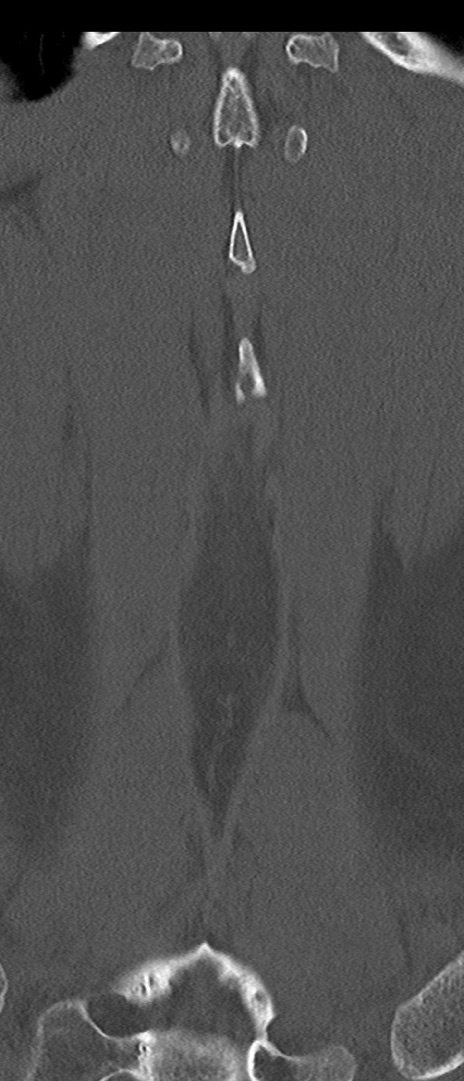

【整形】TIPS症例4 腰椎CT(冠状断像)

腰椎CT